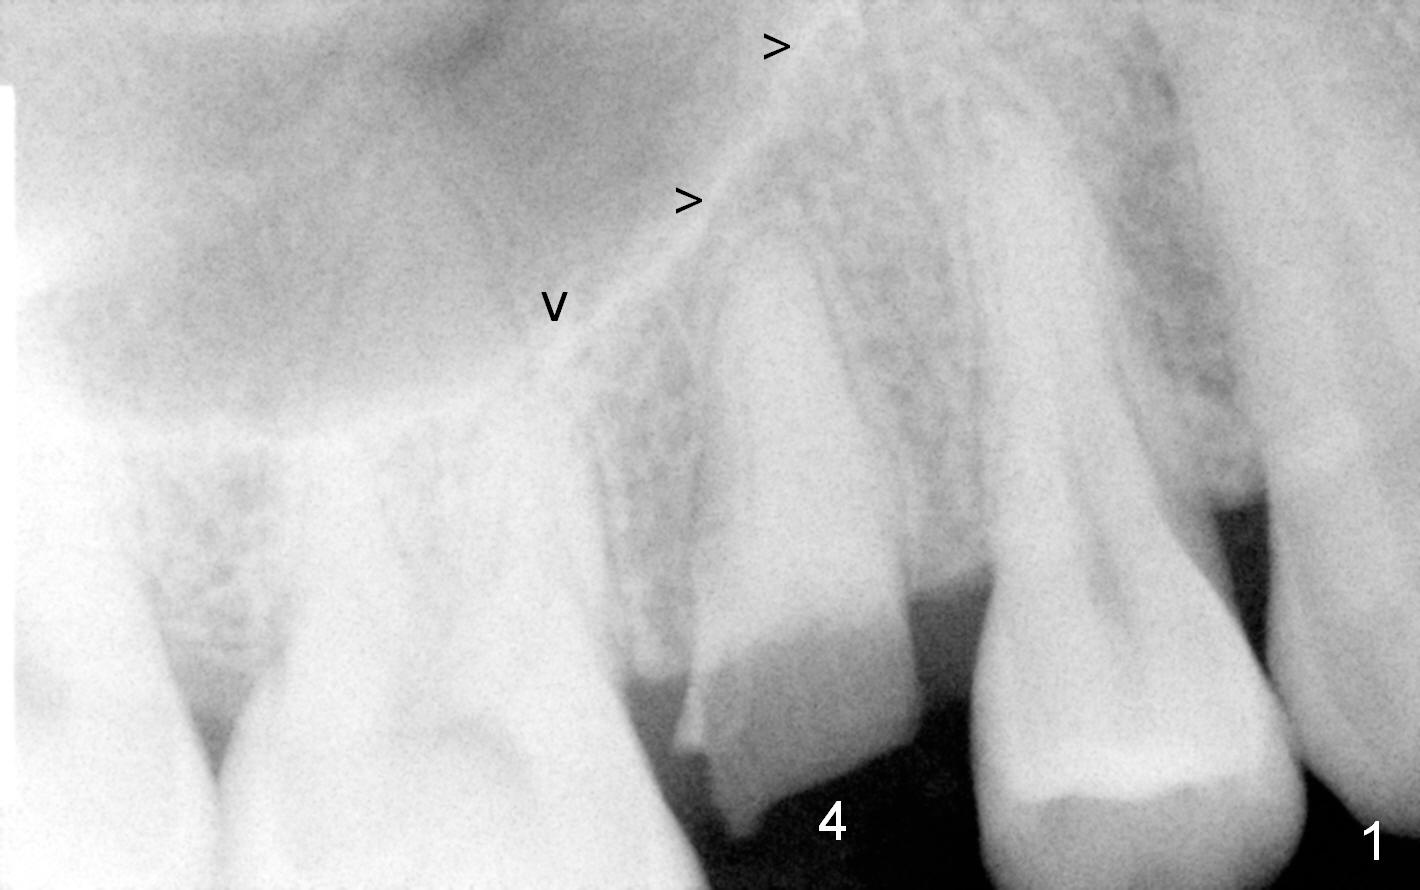

A 52-year-old woman (LP) has postponed extraction and implant for the tooth #4 for 10 years (Fig.1). The socket is oval in cross section, great site for D Implant. D2 (3.5x4.5 mm) short (16 mm, Fig.2) and long (20 mm, Fig.3) implants appear to be fit for the site (no antibiotic). However, placement of the latter involves bone expansion/tapping, which is incompatible with the fearful lady. Let us be gentle (Fig.4).